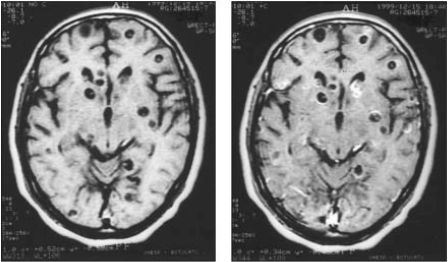

Um homem de 38 anos foi admitido na emergência com 3 episódios de crises convulsivas nos últimos 4 dias. Ao ser examinado, ele não

apresentava déficits focais ou rigidez de nuca. O paciente nega hipertensão, Diabetes Mellitus e alergias. A Ressonância Nuclear Magnética de crânio com e sem contraste evidenciou as imagens a seguir.

Assinale a alternativa que apresenta o diagnóstico provável.